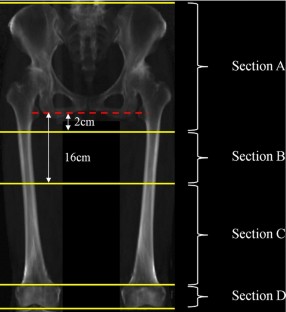

Fig. 2